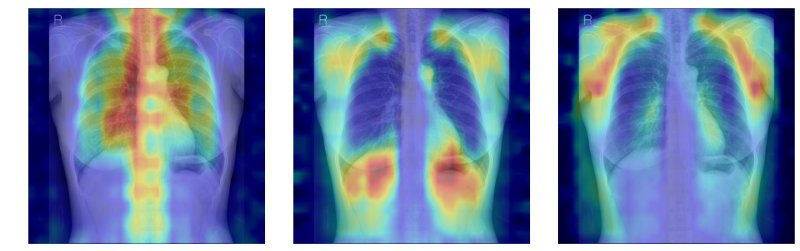

[서울=뉴시스] 흉부X선에서 파운데이션 모델이 골다공증 판독을 위해 주목한 영역을 시각화한 이미지. (사진= 서울대병원 제공)

연구팀은 여기에 더해 AI가 실제로 어떤 뼈를 근거로 삼아 판단하는지까지 확인할 수 있도록 '설명 가능성' 평가 체계를 설계했다. 뼈를 모두 가린 상태에서 특정 뼈 부위를 추가해 성능이 얼마나 향상하는지 확인하는 '차단 분석 방식'과 AI의 주목 영역이 실제 뼈 위치와 얼마나 일치하는지를 계산하는 '유의성 지도 방식'(IoUbone)을 통해, AI가 임상적으로 중요한 뼈 구조를 근거로 판단하는지를 정량적으로 검증했다.